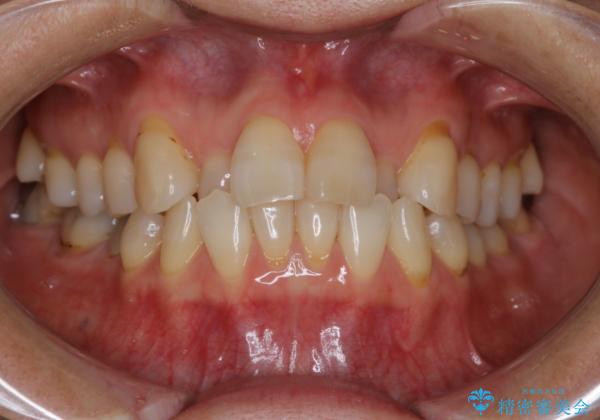

前歯の反対咬合、奥に引っ込んでしまっている歯をインビザラインで治療する

上の前歯の反対咬合があり、治療の途中で下の前歯を乗り越える必要があります。

前歯を乗り越える治療はワイヤーの方が有利ではありますが、インビザライン単独でも行うことができます。